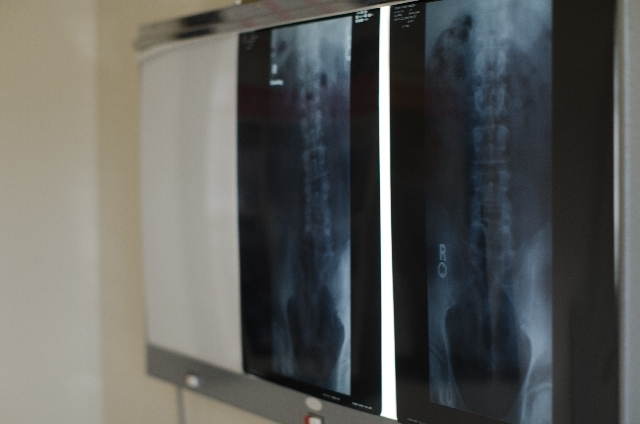

レントゲン検査で確認

完全脱臼のように明らかに足の動きが悪い場合は触診だけで判断されることもありますが、判断が難しい場合はX線撮影(レントゲン)や超音波検査(エコー)を行います。

その結果から、その後の治療方法を決めていきます。こうした検査は、健診などで股関節脱臼の指摘がなくても受けることができます。

前述のチェック項目に該当するなど、脱臼の可能性がある場合は病院で診察と検査をしてもらいましょう。なお、X線撮影での放射線被爆量はわずかであり、問題はありません。